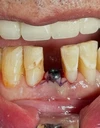

Diş Ağrısı

Diş Çürükleri

Diş Eksikliği

Diş ve Diş eti hastalıkları

Zirkonyum uygulamalar

Implant tedavisi

Porselen uygulamaları